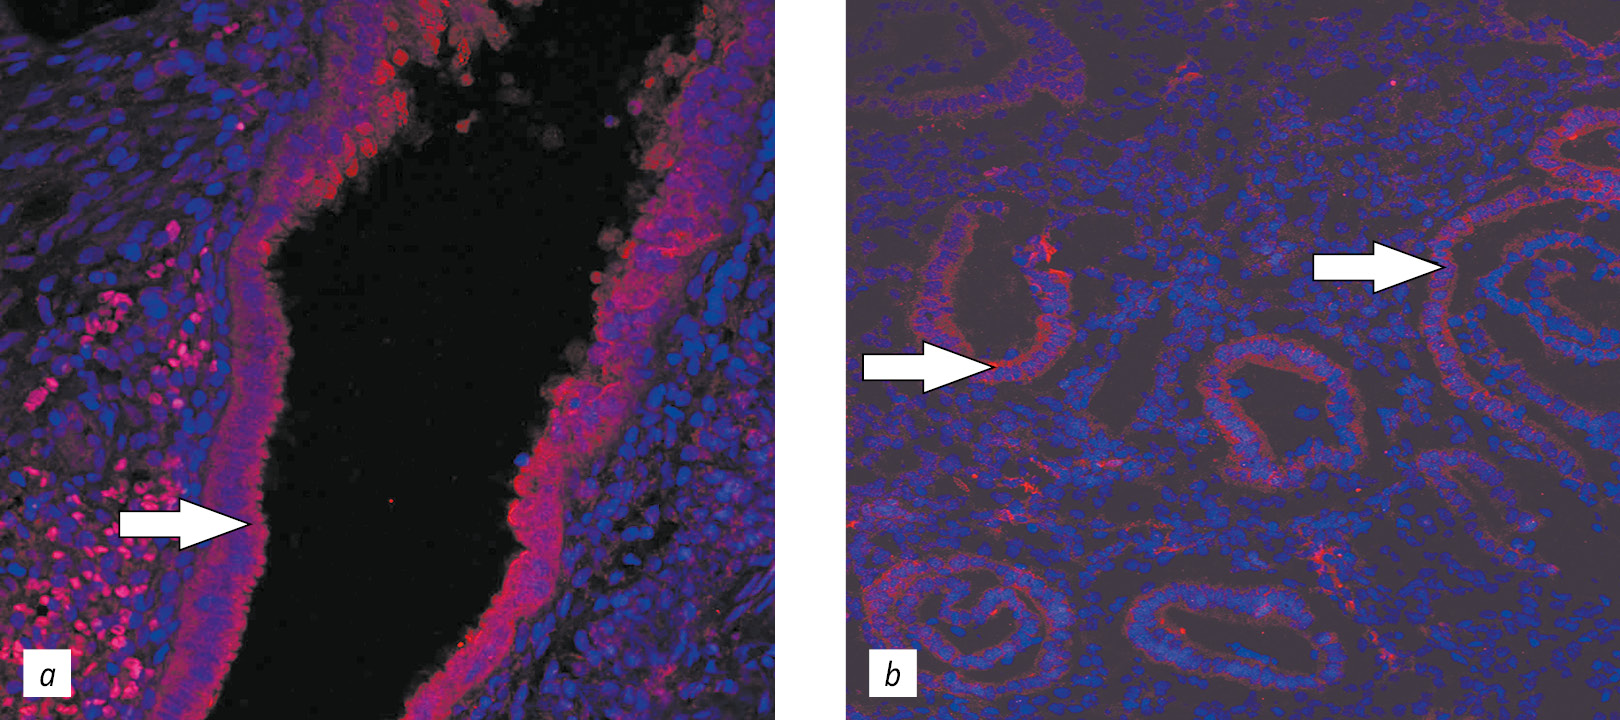

According to the results, the evaluation of the expression of melatonin receptor MTR1 in the eutopic endometrium and the endometrioid heterotopia of EGE patients (Fig. 2) did not significantly differ in the relative expression area and optical density.

When analyzing the relative expression area and optical density of the melatonin receptor MTR2 (Fig. 3), no significant differences were revealed in the eutopic endometrium of EGE patients and endometrioid heterotopia.

Fig. 3. Confocal laser scanning microscopy images of MTR2 melatonin receptor expression in endometrioid heterotopia and the eutopic endometrium in patients with genital endometriosis: a, MTR2 melatonin receptor expression in endometrial heterotopy (red fluorescence), Hoechst (blue fluorescence), ×400 magnification; b, MTR2 melatonin receptor expression in the eutopic endometrium (red fluorescence), Hoechst (blue fluorescence), ×400 magnification

Рис. 3. Экспрессия рецептора мелатонина MTR2 в эндометриодной гетеротопии и эутопическом эндометрии у пациенток с наружным генитальным эндометриозом: a — экспрессия рецептора мелатонина MTR2 в эндометриоидной гетеротопии (красная флуоресценция), Hoechst (синяя флуоресценция), увеличение ×400; b — экспрессия рецептора мелатонина MTR2 в эутопическом эндометрии (красная флуоресценция), Hoechst (синяя флуоресценция), увеличение ×400. Конфокальная лазерная сканирующая микроскопия